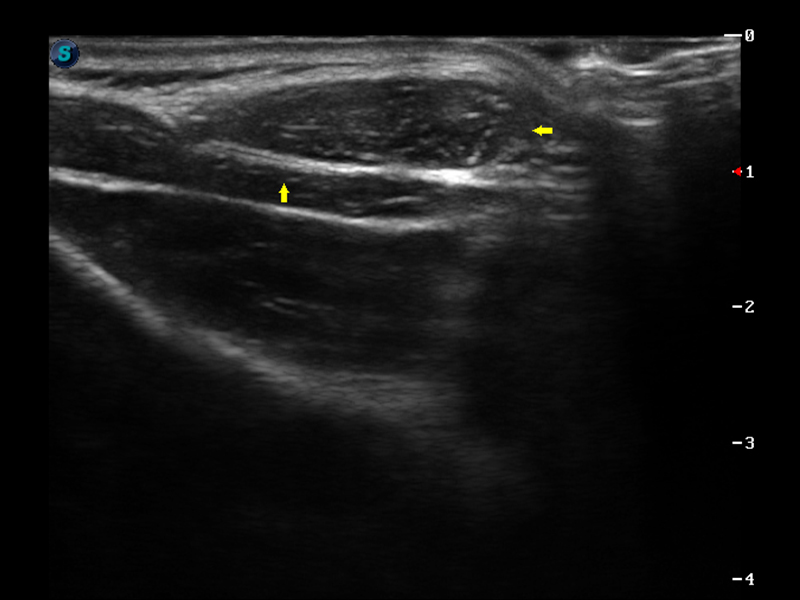

S9便携式彩色多普勒超声诊断仪是竞技宝(JJB)官方网站研发的高端便携彩超设备,外观设计新颖、产品性能卓越。S9在便携超声领域采用了突破传统的触摸屏交互设计,并以先进的软件硬件技术和设计理念,为您带来清晰的图像质量、稳定的工作性能和便捷的操作体验。

μ-Scan微米成像

实时宽景成像